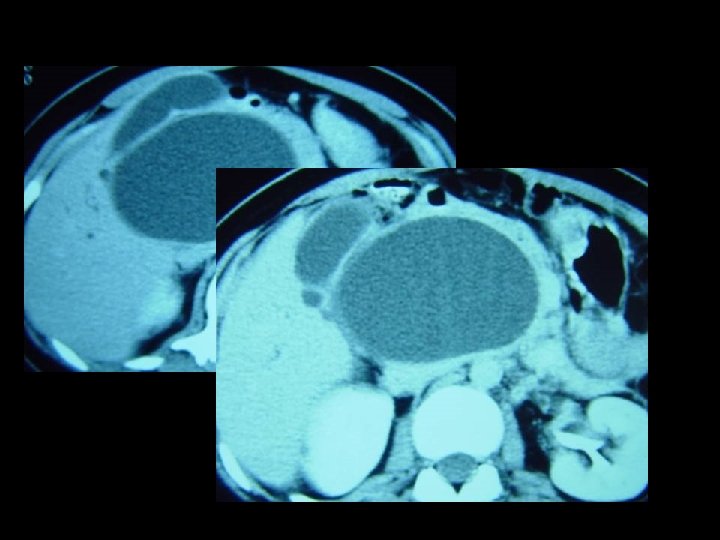

abdominal CT showing an intragastric mass consisting of "compressed concentric rings" with entrapped air, debris and barium within.

Abd. CECT, in the prone position, showing non-adherence of the mass to the stomach wall

• Plain abdominal CT usually shows a mobile intragastric mass consisting of "compressed concentric rings", with a mixed density pattern due to the presence of entrapped air and food debris. • Often small collections of barium from a previous upper GI barium study may be interspersed within the mass. • The demonstration of a normal gastric wall and the free mobility of the mass on rescanning, after alteration of the patient’s position and administration of oral contrast, rule out origin from the gastric wall.